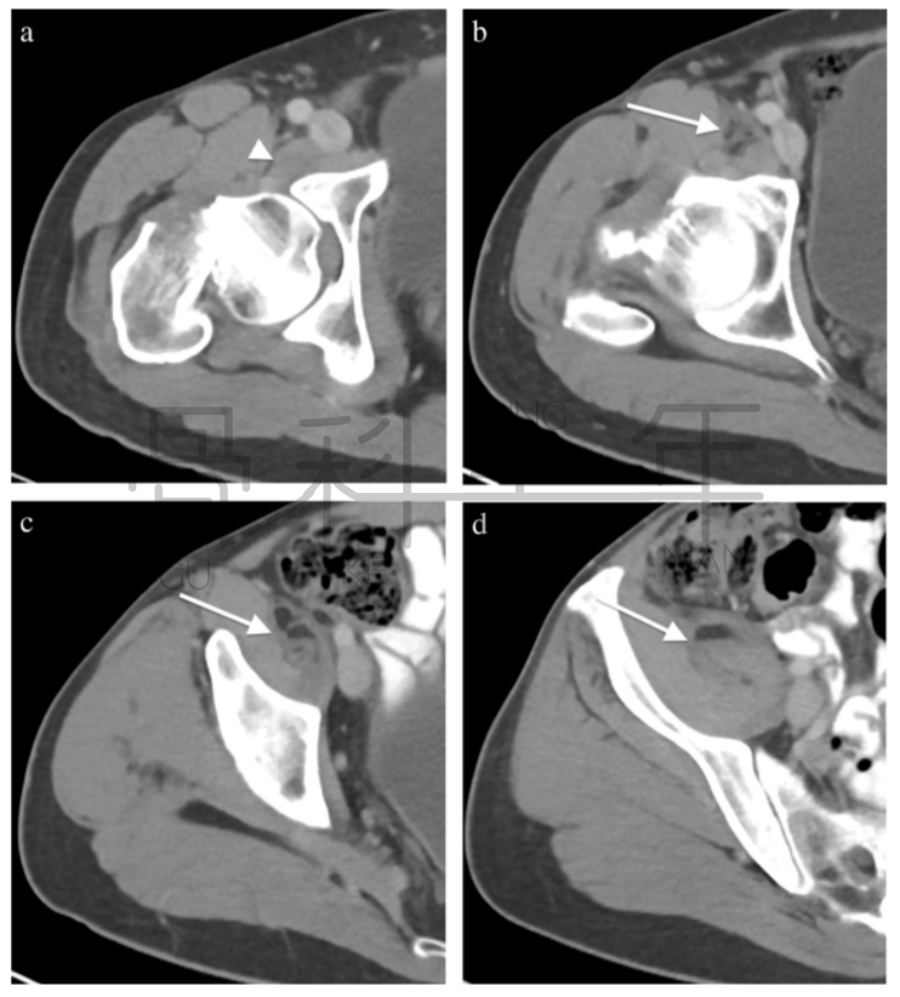

病例5股骨颈骨折,在CT横断面软组织窗上可见在髂腰肌内出现积脂血症表现。

病例6 一例82岁髋部外伤患者,非移位股骨颈骨折,在CT横断面可见积脂血症,MR证实股骨颈骨折。关节积脂血症在非移位股骨颈骨折的识别中作用明显。